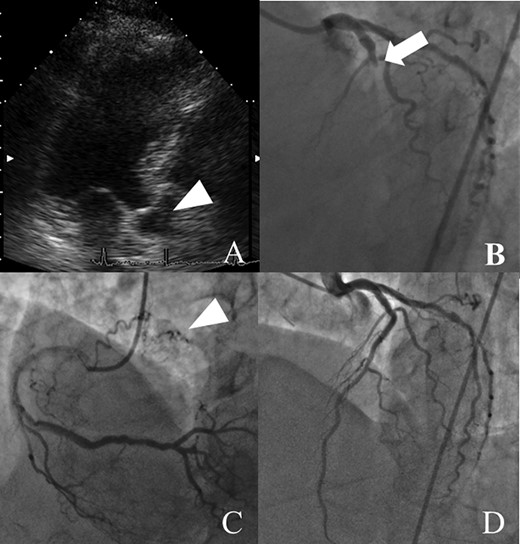

An 84-year-old woman was referred to our institution because of an IAS tumor detected on follow-up echocardiography (Fig. 1A). She had a history of acute myocardial infarction (MI) at the age of 73 years. Although she had few coronary risks, the left anterior descending (LAD) artery was totally occluded at the proximal segment (Fig. 1B). Further, no arteriosclerosis was found in other coronary arteries (Fig. 1C). Percutaneous coronary intervention was successfully performed, and follow-up coronary arteriography (CAG) showed no restenosis (Fig. 1D). She had no symptoms of congestive heart failure or murmur; however, transthoracic echocardiography incidentally revealed an IAS tumor presenting as a solid and immovable mass of 14 × 16 × 12.1 mm, while transesophageal echocardiography showed an IAS solid tumor with calcification (Fig. 2A–C). Enhanced computed tomography revealed a low-density area with a spot of high density, leading to suspicion of a cardiac cyst, thrombus or myxoma (Fig. 2D). Our cardiac team concluded that tumor pathological examination was necessary for an accurate diagnosis.

Preoperative findings before percutaneous coronary artery intervention. (A) CAG shows the totally occluded left coronary artery suggesting embolization by thrombus or tumor (arrow). (B) Follow-up CAG shows no signs of arteriosclerosis, such as diffuse constriction. (C, D) Six years before presentation, right coronary artery angiography shows a tumor with feeding vessels, and echocardiography shows an IAS tumor (arrowheads), suggesting that the tumor was present at that time.

Retrospectively, the patient’s past medical history suggested a myxoma. The patient was healthy with few coronary risk factors; however, she had experienced an acute MI 6 years before surgery. CAG had shown an intact coronary artery, except for total occlusion of the proximal LAD (Fig. 1A). Follow-up CAG showed no restenosis of the LAD and intact distal LAD (Fig. 1D). These findings suggest that the patient had an acute MI due to myxoma embolization rather than atherosclerotic disease and showed a pale contrast effect suggesting the presence of feeding vessels of a tumor (Fig. 1C). We thus speculate that the myxoma had existed from before and caused acute MI.